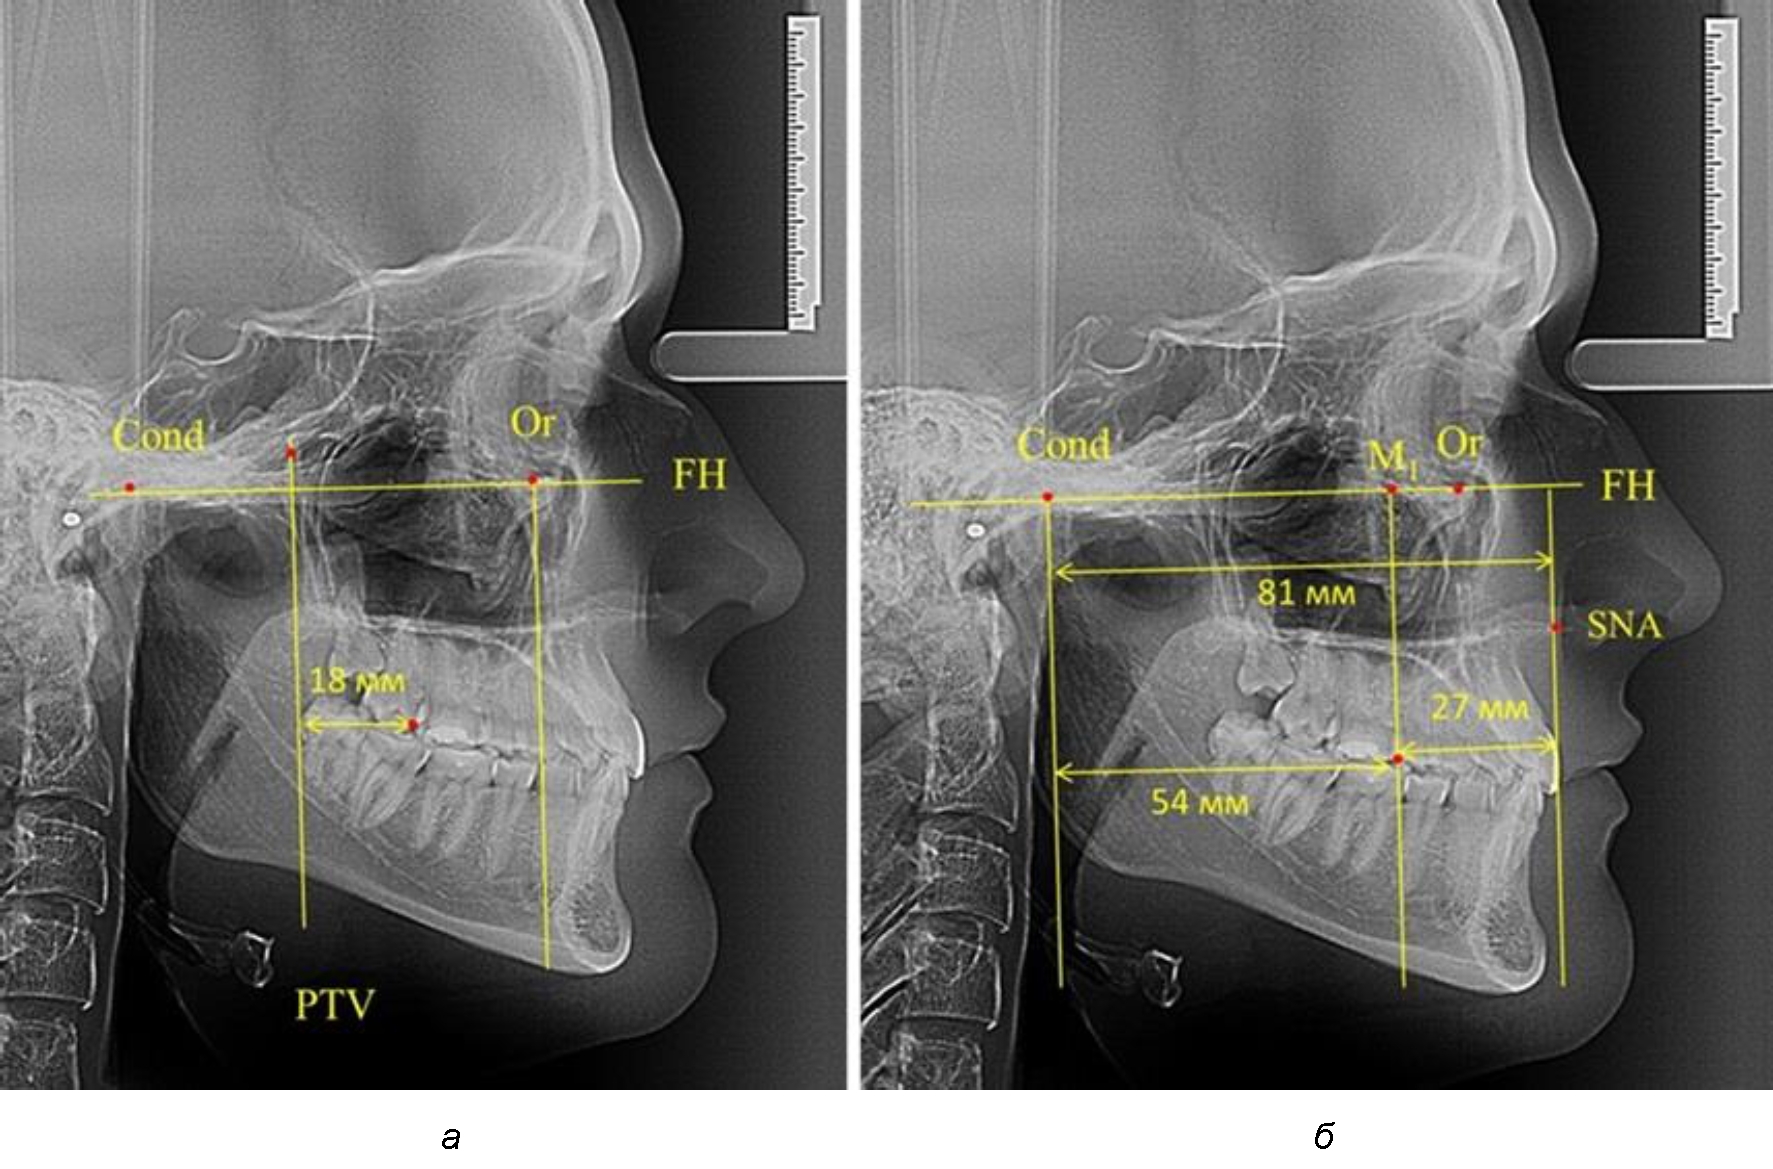

В то же время при увеличенном расстоянии от крыловидной вертикальной плоскости PTV до дистальной поверхности верхнего первого постоянного моляра, равное 23 мм, сагиттальный размер гнатического отдела составил 92 мм. При этом отношение кондилярно-спинального расстояния к кондилярно-молярному размеру (30,5), так же, как и при малых размерах, было близким к коэффициенту 1,5, что представлено на рис. 3.

Рис. 3. Особенности положения первых моляров по R. E. McDonald (а) и по предложенному методу (б) при увеличенном молярно-крыловидном расстоянии